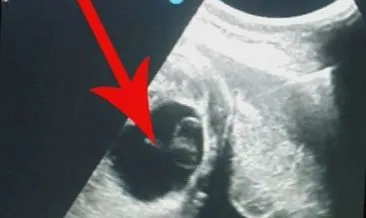

Yumurtalık kistleri türlerine göre iyi ya da kötü huylu olarak ayrılabilmektedir. Yumurtalık kisti neden olur kimlerde meydana gelebilir. Büyük kistler için ve kötü huylu olma ihtimali olan kistlerin çıkarılması için kullanılan yöntemdir. Bu testler sayesinde iyi huylu ya da kötü huylu kistler tespit edilmiş olur.

İyi huylu ve kötü huylu kist nasıl anlaşılır. Yumurtalık kisti çeşitleri ve belirtileri.